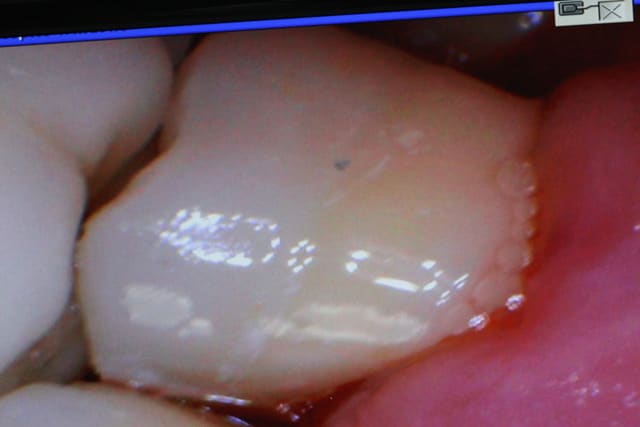

un cas réalisé depuis : une endocouronne réalisée la semaine dernière sur une nécrose d'origine paro ,

usinage + cuisson 35 minutes => surfaçage arcade complète + essayage du biscuit

pose 10 minutes